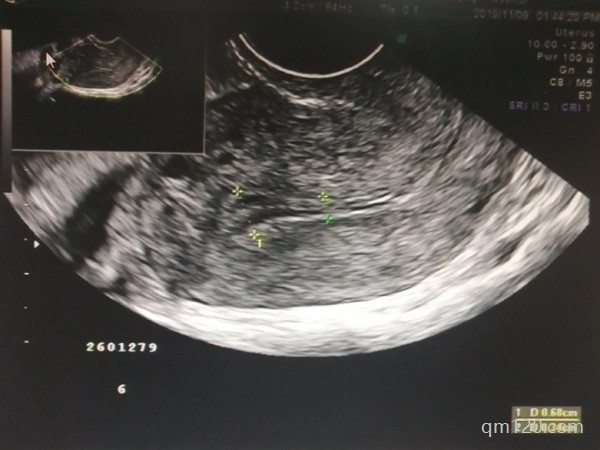

在試管嬰兒治療中,卵泡的數(shù)量常被視為評估成功機會的一個關鍵因素。對于42歲的女性來說,如果檢查發(fā)現(xiàn)只有3個卵泡,是否還能進行試管嬰兒治療?高齡女性的生育挑戰(zhàn)1、...

本人是一位高齡女性,今年有42歲了,但還未生育子女,去醫(yī)院做過生育檢查,醫(yī)生說是卵泡數(shù)量少,建議我們先通過使用激素藥物改善后再做三代試管嬰兒,我想知道這種方法可...

影響孩子發(fā)育的原因有很多種,你的卵子發(fā)育不成熟,有可能是因為卵巢功能不好的原因?qū)е?,也有可能與內(nèi)分泌激素也有關系,或是其他原因有關,需要到醫(yī)院做一下進一步檢查,...

然而對于高齡且卵泡數(shù)量較少的女性來說,她們往往會面臨更大的挑戰(zhàn)。那么高齡卵泡少的女性還能在廣州做試管嬰兒嗎?成功率又是多少呢?本文將為您詳細解答這些問題,并提給...

然而在實際操作過程中,尤其是對于高齡女性來說,試管促排階段可能會遇到卵泡數(shù)量偏少的問題,這無疑給期待新生命的家庭帶來了一定的壓力和困惑。不過,請放心,針對這一問...